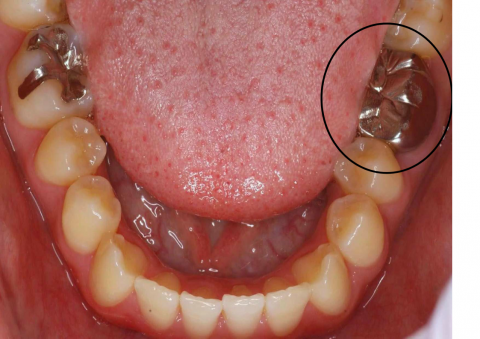

CAD / CAM (Cerec 3D)

CAD / CAMシステムにより様々なマテリアルのミリング(削りだし)を正確に行うことができます。